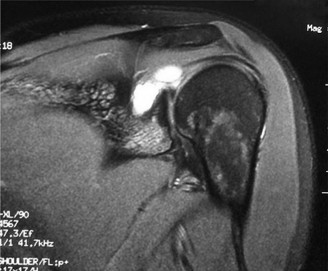

You send the patient for an MRI, which is shown in Figure 2–66.

Figure 2–66

The correct answer is (C). The patient’s clinical examination findings of isolated

weakness in external rotation and atrophy of the infraspinatus muscle point to suprascapular nerve entrapment at a location past the exit point for the branch to the supraspinatus muscle. Also, MRI reveals a posterior labral tear with a paralabral cyst that is compressing the suprascapular nerve at the spinoglenoid notch. Choice A, while fitting with the patient’s clinical examination, does not fit with the MRI showing paralabral cyst. Choices B and D are incorrect because entrapment of the suprascapular nerve at the suprascapular notch by scapular body fracture or by the transverse scapular ligament (more common) would lead to weakness/atrophy in both supraspinatus and infraspinatus muscles as the suprascapular notch is proximal to the nerve branch point to the supraspinatus muscle.